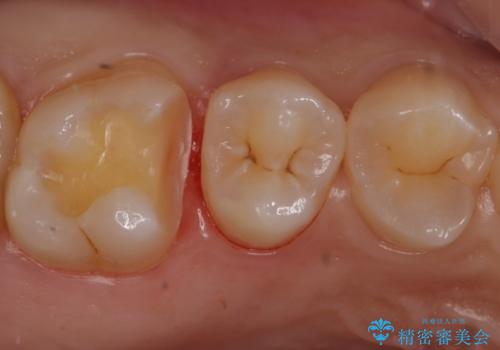

歯と歯の間の虫歯 セラミックインレーでの治療

- 矯正前の虫歯治療です。

歯と歯の間に虫歯があったためセラミックインレーで治療をしていきました。

- 右上6 セラミックインレー 77,000円費用は治療当時の料金となります